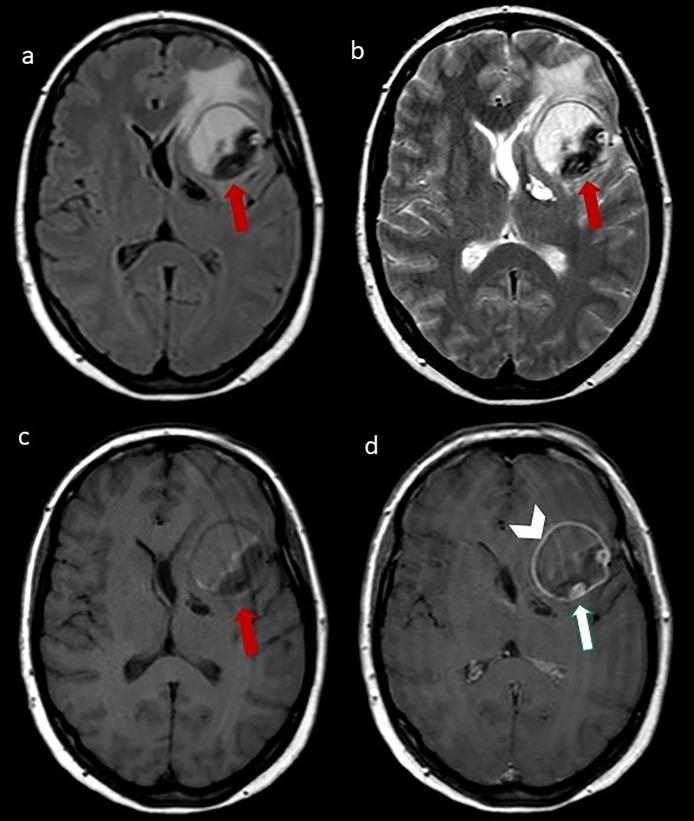

Giant serpentine aneurysms are rare huge and partially thrombosed aneurysms, with an eccentric tortuous intra-aneurysmal vascular channel. Surgical treatment is often necessary due to the great mass effect. We describe a case of a left-handed woman with a giant serpentine aneurysm of the left middle cerebral artery whose management was complex. The challenge was to exclude the aneurysm from circulation, reduce the mass effect, and, mostly, preserve the language function. Since the patient was left-handed the language dominance needed to be assessed; functional MRI (fMRI) and Wada test (WT) showed a right dominance. Surgical treatment was performed, as a complication, the patient developed left fronto-basal ischemia with a slight paresis of the right hand but without any language deficit. Our case shows the importance of a multidisciplinary team in patient management, with a pivotal role of neuroradiological functional tests in presurgical planning.

巨大蜿蜒状动脉瘤是罕见的巨大且部分血栓形成的动脉瘤,具有偏心迂曲的瘤内血管通道。由于巨大的占位效应,通常需要进行手术治疗。我们描述了一例左手中风的女性患者,患有左大脑中动脉巨大蜿蜒状动脉瘤,其治疗过程复杂。面临的挑战是将动脉瘤排除在循环之外,减轻占位效应,并且最重要的是保留语言功能。由于患者是左利手,需要评估语言优势半球;功能磁共振成像(fMRI)和Wada试验(WT)显示为右侧优势半球。进行了手术治疗,作为并发症,患者出现左额底部缺血,右手轻度无力,但无任何语言缺陷。我们的病例显示了多学科团队在患者管理中的重要性,神经放射学功能测试在术前规划中起着关键作用。